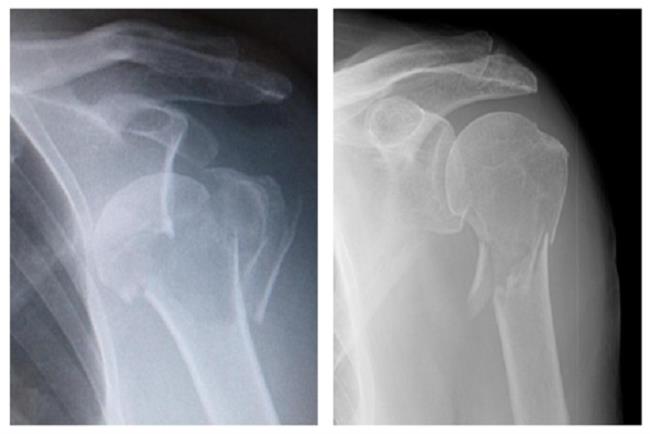

צילום רנטגן במנח קדמי-אחורי של הכתף. ניתן לראות את שלוש עצמות הכתף: עצם הזרוע, עצם השיכמה ועצם הבריח. מפרק הכתף הראשי נוצר בין ראש עצם הזרוע למכתש בעצם השכמה (1), מעליו מפרק נוסף בין קצה עצם הבריח לזיז הקדמי של עצם השיכמה (2).

צילומי כתף של שני מטופלים שונים לאחר חבלה משמעותית לכתף. בצילום מימין ניתן להתרשם משבר חוץ מפרקי בעצם הזרוע המקורבת, מפרק הכתף עצמו והמשטח המפרקי נותרו שמורים. בצילום משמאל ניתן לראות פריקה קדמית של ראש עצם הזרוע עם מספר קווי שבר תוך מפרקים.